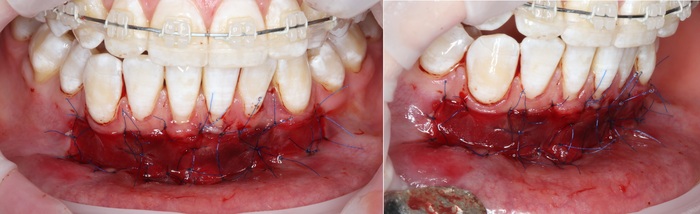

Далее проведена пластика десны, снова два месяца ожиданий и установка временной коронки:

Ну, такое, согласен, но это начало.